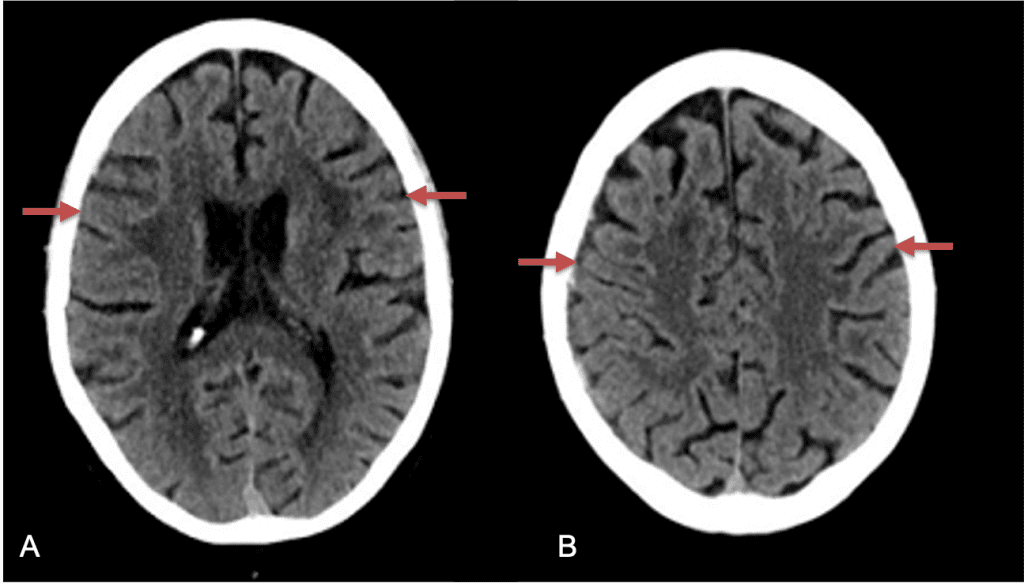

CT follow-up at 1 week demonstrates early resorption. 2 weeks post MMA embolization, resolution of the left subdural collection with new small thin acute hemorrhage in an otherwise stable right subdural collection is observed (Figure 3. A and B).

Figure 3. A) 1 week post MMA embolization demonstrating decreasing thickness bilaterally B) 2 weeks post MMA demonstrates resolution on left, with small new acute component on right with overall decreased thickness.

Clinically, the patient improved over the few weeks with the occasional transient twinge of a headache, but resolution of dizziness. Follow-up CT at 10 weeks demonstrated complete resolution of the bilateral subdural hematomas with our patient completely asymptomatic and back to all of her activities of daily living. Considering her history of thrombocytopenia and CLL, we will continue to monitor her into the future and are excited about her progress and recovery. (Figure 4. A and B)

Figure 4. A and B) – 10 weeks following embolization demonstrates complete resolution of bilateral collections both acute and chronic.